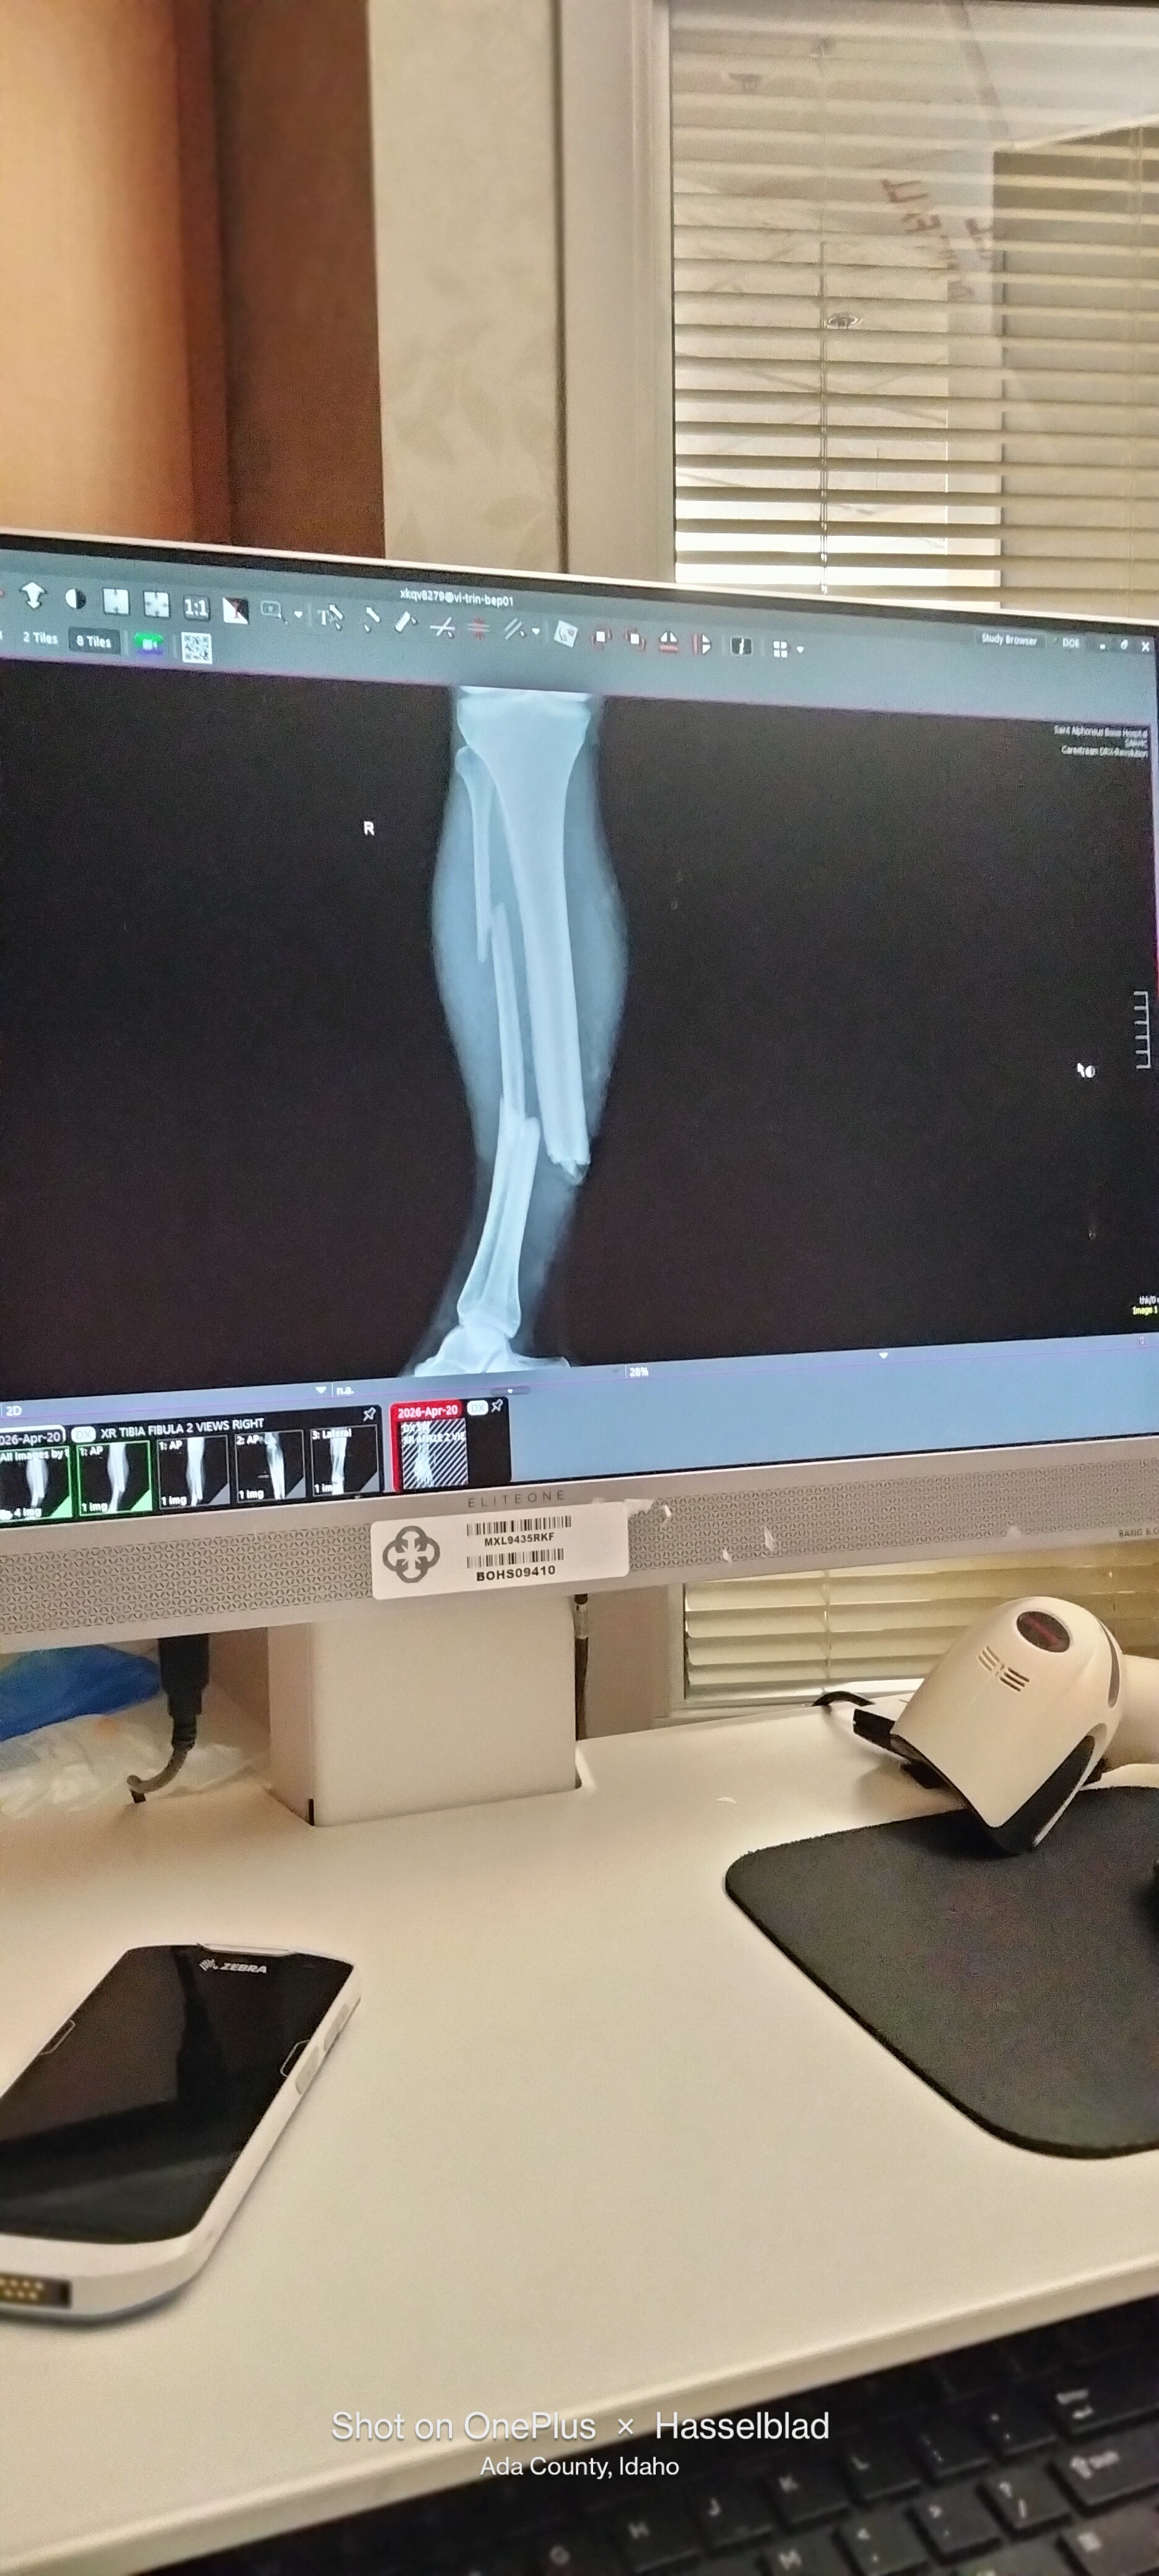

As some may have already heard, my boyfriend Nat was in a horrible motorcycle accident on Monday April 20th. He is going to have a long road to recovery with his leg broken in three places, a fractured rib, small fracture in his spine, a fractured wrist, abrasions on his lungs, and an AC ligament tear in his shoulder and rotator cuff. He has already been through one surgery on his leg, with a possible future surgery depending on how everything heals, as it is considered a high risk recovery and can have complications.